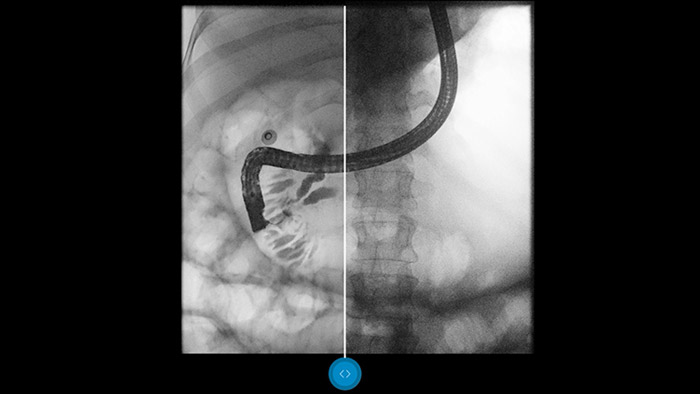

Compare lado a lado com um processamento de imagens convencional e veja os benefícios para si.

O Dynamic UNIQUE tem supressão inteligente do ruído espaciotemporal, estabilização temporal da luminosidade e melhoria da imagem a vários níveis em tempo real, para permitir um processamento de imagens de alta qualidade em tempo real.